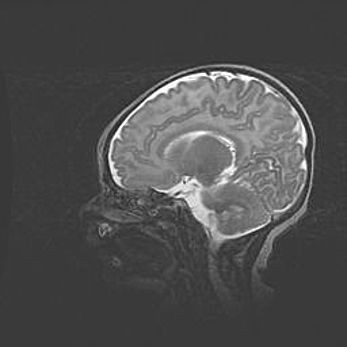

Аномалия Денди-Уокера. Признаки гипоплазии мозолистого тела.

Возраст: 5 месяцев 3 дня

Вес: 5550 г

Пол: мужской

Окружность головы: 39 см

Срок гестации: 40 недель

Аномалия Денди-Уокера – это порок развития головного мозга, для которого характерна триада симптомов: гипотрофия или аплазия червя мозжечка и/или полушарий мозжечка, расширение четвёртого желудочка с формированием ликворной кисты задней черепной ямки, гипертензионная гидроцефалия различной степени.

Гипоплазия мозолистого тела относится к дефектам внутриутробного этапа развития мозговой ткани, возникающим в процессе закладки структур головного мозга, что происходит на начальных этапах развития эмбриона.